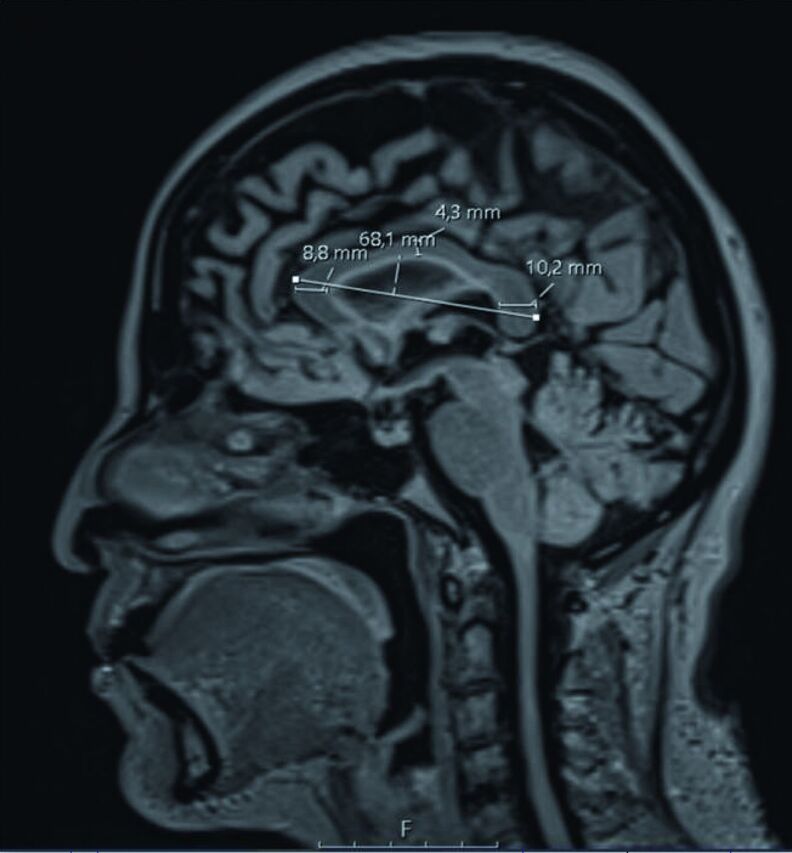

Methods: In this study, 150 MS patients (disease duration 12.6±5.9 years) and 150 healthy control subjects were scanned. Corpus callosum index was manually measured from the mid-sagittal slices on MRI. A deep learning architecture-based U-Net model was used for automatic corpus callosum segmentation from 2D brain MRI.